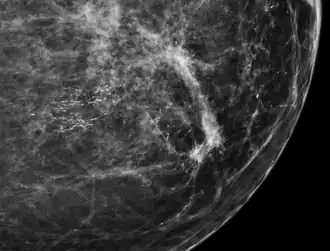

-

Calcium phosphate microcalcifications in non-neoplastic breast tissue.

Calcium phosphate microcalcifications in non-neoplastic breast tissue. -